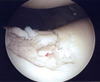

変形性膝関節症

変形性関節症は軽く痛みがでてから5~10年の経過でゆっくり進行する病気です。軟骨は今の再生医学をしてもまだ完全な回復は望めない物質です。65歳以上の高齢者ではたとえ症状がなくてもX線では70%に変形性変化が見られます。痛みがたまに出ては自然にとれてしまう位でも軽度変形に多くは進んでいます。初期関節症から治療しないと10~15年で高度関節症になります。

軟骨の浅い亀裂

軟骨中度障害

膝蓋骨面の中度軟骨障害

広範囲の軟骨障害